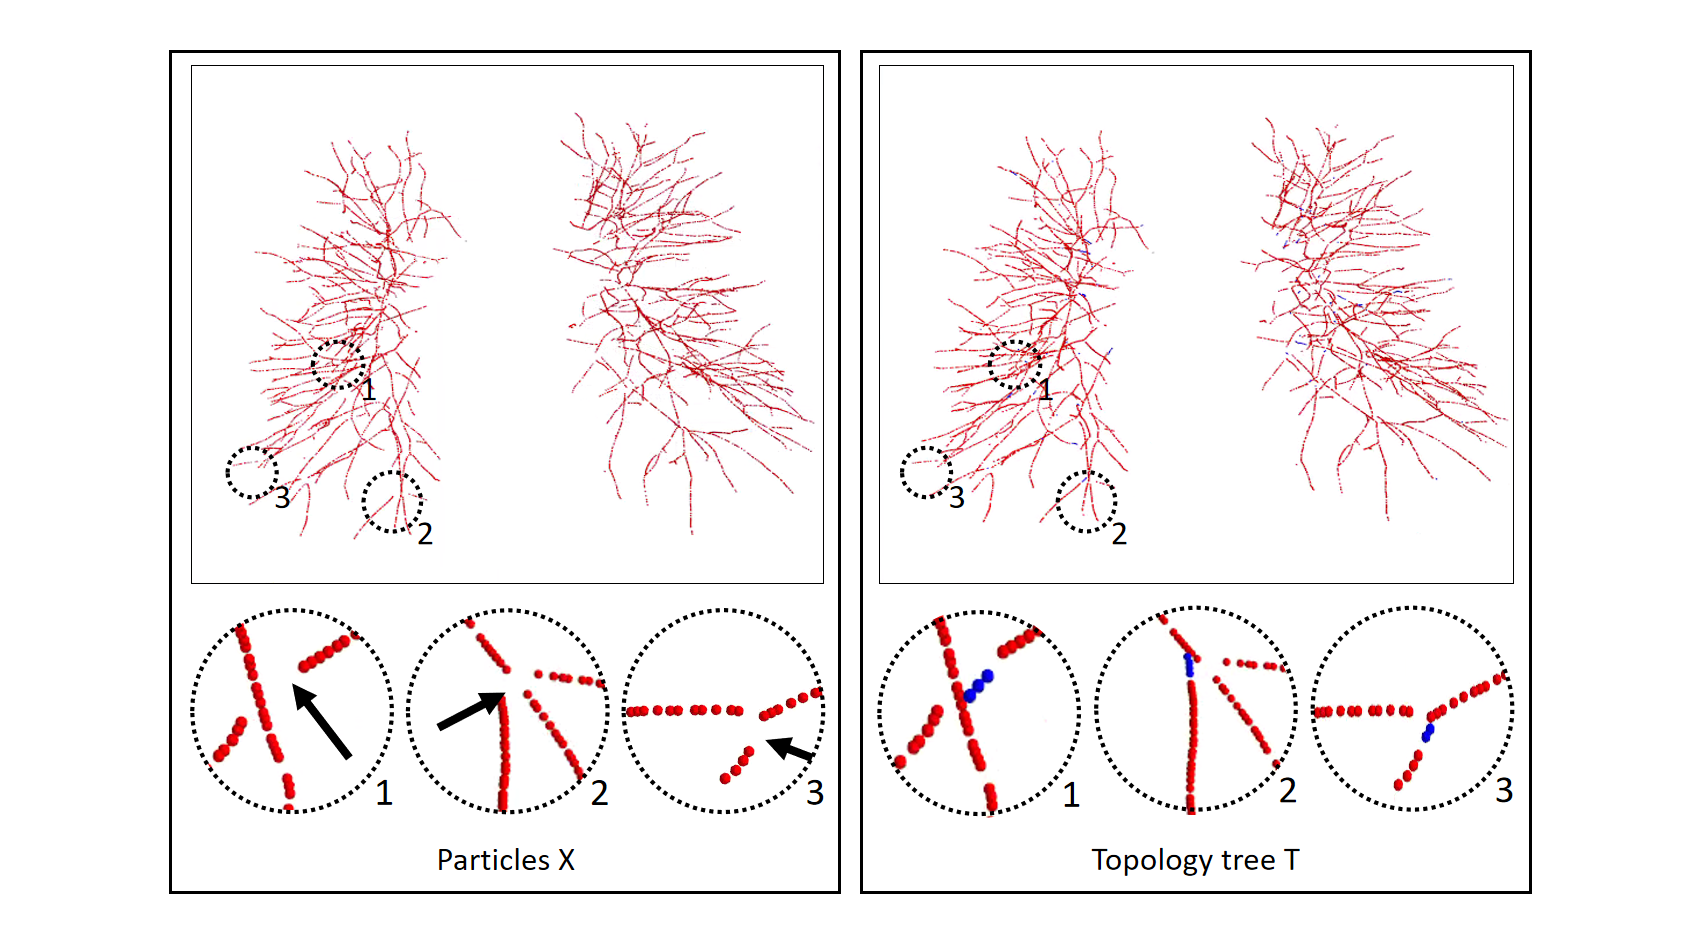

Based on the extracted topology tree, the information of each particle point is used to construct the graph structure we need. Particle points can be divided into three types: terminal points, branch points, and bifurcation points (or attached points, false-positive points). Through the category of particle points and the parent-child node relationship between particles, we redefined a graph T = composed of nodes X = {} and edges = {}. And then, in order to train the Twin-Pipe network, we can extract each branch subgragh from graph T, and each branch subgragh is either an artery or a vein.

We propose that the Twin-Pipe network is expected to learn the difference of A/V characteristics caused by different levels and improve the accuracy of the preliminary classification. In this paper, a Twin-Pipe network is designed, in which one pipe network trains the full vessel graph to learn the image information and global connectivity, and the other pipe network specially trains the terminal vessel graph to learn the terminal structure characteristics. Finally, the preliminary classification results are obtained through the mutual correction module. The terminal vessel graph is the set of terminal branches in the full vessel graph, and the extraction process is shown in Fig. 9.

2.3 Optimizer and A/V Result

Though the Twin-Pipe network can learn local, global and connectivity information, spatial inconsistency may still occur during classification. Therefore, after the preliminary classification of Twin-Pipe network, we apply a topology optimizer base on the vascular tree spatial structure to refine the classification. First of all, for the local patch corresponding to each particle, the preliminary probability is given by the Twin-Pipe network. If the probability is greater than 0.5, the node is an artery. otherwise, it is a vein. Then, based on the subtrees extracted in this paper, whether each subtree belongs to an artery or a vein depends on the confidence level of the current subtree. Finally, the branch confidence of each subtree is calculated. When the subtree category and the branch category are inconsistent, and the branch has higher confidence, appropriate pruning is performed to correct the predicted results. The confidence calculation depends on the initial number of predicted arteries and veins on the subtree or branch.

Finally, the topology optimizer extracts the topology subtree and topology branch refinement results by the method in Section 2.3. The results of a topology subtree and topology branch are shown in Fig. 9. Then, we use topology subtrees and topology branches for postprocessing. As shown in Table 3, the proposed topology optimizer is superior to the subtree-based and branch-based topology optimization in accuracy. Fig. 14 and 15 show the reconstructed results of different topology strategy optimizers. The results in Fig. 14 show that when the number of points on the branch is small, and the branch-based topology optimization method is prone to predict errors. This finding is mainly because the branch-based refinement strategy focuses on the relationships within the branches and ignores the topological relationships between branches. As shown in Fig. 15, topology optimization based on subtree strategy is prone to prediction errors in the case of arterial-vein intersection. This finding is mainly because the arterial/venous intersection point in the extraction process of topological subtree is easily mistaken for the bifurcation point of arterial subtrees due to the complex structure of the vascular tree, arteries and veins interweave, and finally the venous branches are classified as arterial subtrees, resulting in the classification error.